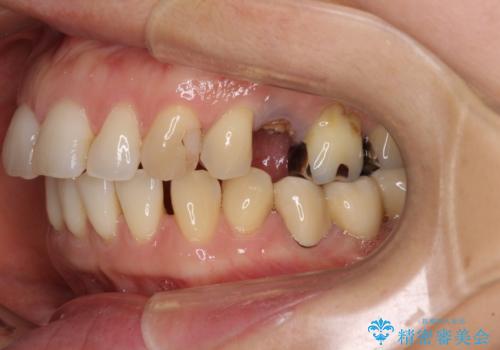

- 飛び出した上顎前歯と正中のズレを気にして来院された患者様です。

上顎正中が右側にずれていたので、むし歯が酷く抜歯が必要な左側臼歯を抜歯して正中を改善することとしました。

左下には新しいセラミックのブリッジが装着されていたため、ブリッジを壊さずに改善できるところまで咬み合わせを改善していくこととしました。

右上小臼歯は銀歯が装着されており、ワイヤー矯正の装置が装着できないため、事前に仮歯に変えてから矯正治療を行い、その後オールセラミッククラウンにて補綴治療を行いました。